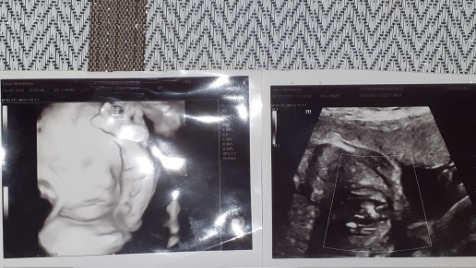

pomagam.pl/a7a98y💛💛💛 Drodzy Ludzie - Dobrego, Wielkiego, Pomocnego Serca. ❤ Zwracam się do Was z Ogromną Prośbą🙏 🙏🙏o Pomoc w Uratowaniu Mojego Nienarodzonego jeszcze Synka, który już teraz w brzuszku ma wadę Serduszka. 💔💔Mam na imię Natalia. Jestem teraz samotną matką, którą zostawił ojciec dziecka jak się dowiedział że jestem w ciąży. Kazał usunąć ciążę😭🥺Rodziny nie mamy. Rodzice już nie żyją 😥 i zostalam sama z Synkiem na tym świecie. Pracowałam aż do 6 tego miesiąca będąc w ciąży. Na badaniu USG oraz Prenatalnym dowiedziałam się że Synek ma wadę Serduszka 💔💔i po porodzie będzie konieczny zabieg lub operacja.😭😭 Zostało nam bardzo mało czasu do porodu. Termin porodu mam wyznaczony na 26 września. Zebrane pieniążki bęndow przeznaczone na ratowanie i koszty leczenia mojego Synka. Wszystkie badania, wizyty, paragony, koszty lekarstw z apteki będę udostępniać na stronie. Liczy się każda złotówka. Z góry Dziękuję Wam Ludzie Dobrego Serca❤ za każdą wpłaconą kwotę. Z całego Serca ❤❤Mojego i Synka życzę Wam Zdrowia - bo Ono jest w życiu najważniejsze. ❤❤❤🙏🙏🙏 pomagam.pl/a7a98y‼‼